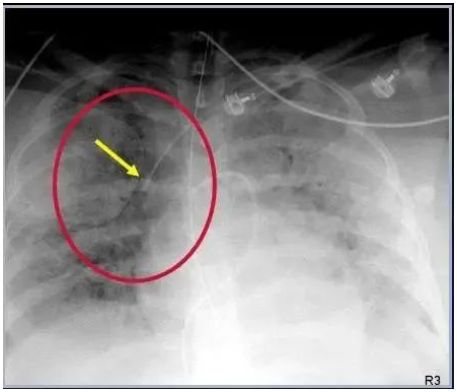

图:肺动脉漂浮导管在左肺动脉内折返(红箭),末端进入右心室(绿箭)。